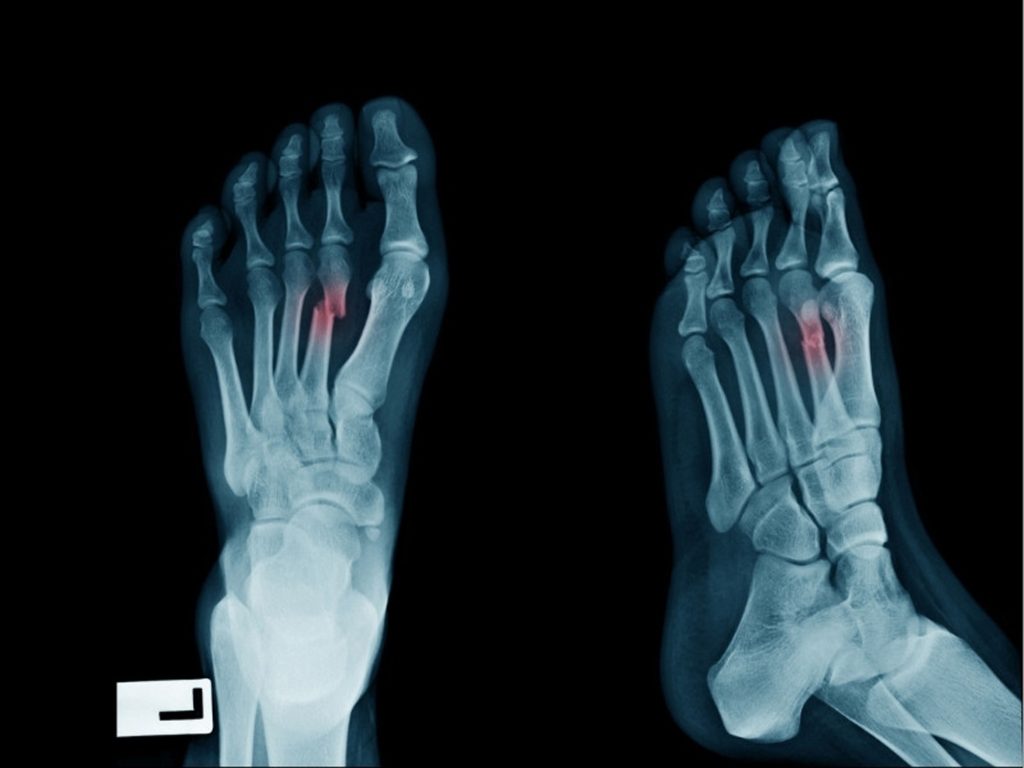

Kırık, kemiğin bütünlüğünün bozulması yani kemiğin çatlaması ya da tamamen parçalanması durumudur. Kırıklar genellikle darbe, düşme ya da yüksek basınca maruz kalma sonucu ortaya çıkar. Özellikle yaş ilerledikçe kemiklerin dayanıklılığı azalır ve kırılma ihtimali artar.

Kırık, doğru şekilde tedavi edilmezse kemik yanlış kaynayabilir ve bu da kalıcı fonksiyon kayıplarına yol açabilir.